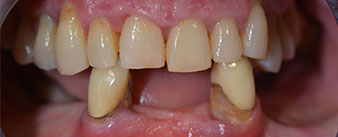

The 64-year-old patient presented with residual dentition of teeth 38, 33 and 43 and a clasp denture in the mandible (Fig. 1 and 2).

Fig. 1